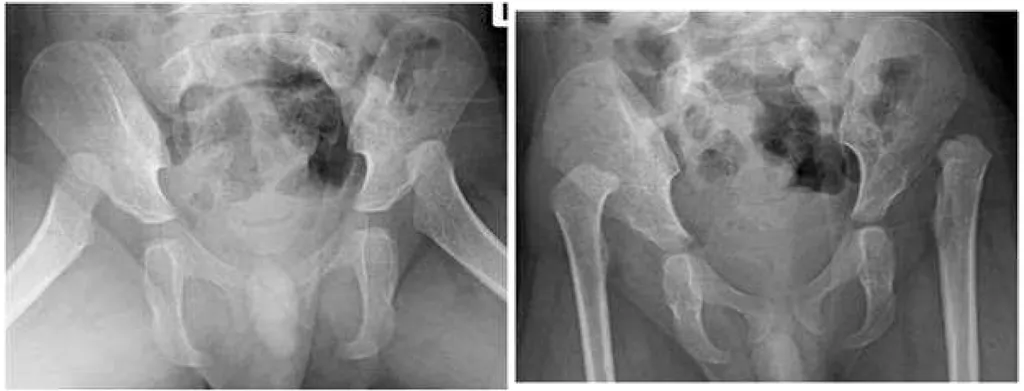

【108-2 醫學(五) 第74題】3歲小男生走路搖搖擺擺,步態不穩,髖關節X光檢查如附圖,最可能的診斷為何?